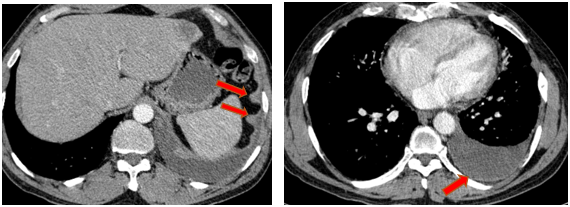

-         Chụp cắt lớp vi tính ổ bụng (08/2025): Nhu mô gan phải có vài nốt, nốt lớn nhất hạ phân thùy VII có nốt giảm tỷ trọng, ngấm thuốc kém sau tiêm đường kính 24mm, hạ phân thùy II, III có nốt 2 giảm tỷ trọng đường kính 13mm và 27mm. Các ổ đặc xương rải rác đốt sống ngực thắt lưng, xương cùng và xương chậu hai bên – theo dõi tổn thương thứ phát

Hình 04: Nhu mô gan phải có vài nốt, nốt lớn nhất hạ phân thùy VII có nốt giảm tỷ trọng, ngấm thuốc kém sau tiêm đường kính 24mm, hạ phân thùy II, III có nốt 2 giảm tỷ trọng đường kính 13mm và 27mm

Hình 05: Các ổ đặc xương rải rác đốt sống ngực thắt lưng, xương cùng và xương chậu hai bên – theo dõi tổn thương thứ phát

-         Chụp cắt lớp vi tính ổ bụng (11/2025): Nhu mô gan phải có vài nốt, nốt lớn nhất hạ phân thùy VII có nốt giảm tỷ trọng, ngấm thuốc kém sau tiêm đường kính 8mm, hạ phân thùy II, III có nốt giảm tỷ trọng đường kính (tổn thương giảm đáng kể so với phim chụp ngày 08/2025). Các ổ đặc xương rải rác đốt sống ngực thắt lưng, xương cùng và xương chậu hai bên.

Hình 11: Tổn thương ngấm thuốc kém nhu mô gan hạ phân thùy II giảm đáng kể kích thước

Hình 12: Tổn thương ngấm thuốc kém nhu mô gan hạ phân thùy VII giảm đáng kể kích thước

+      Các tổn thương ngấm thuốc kém do di căn tại gan giảm kích thước đáng kể (27mm còn 8mm)